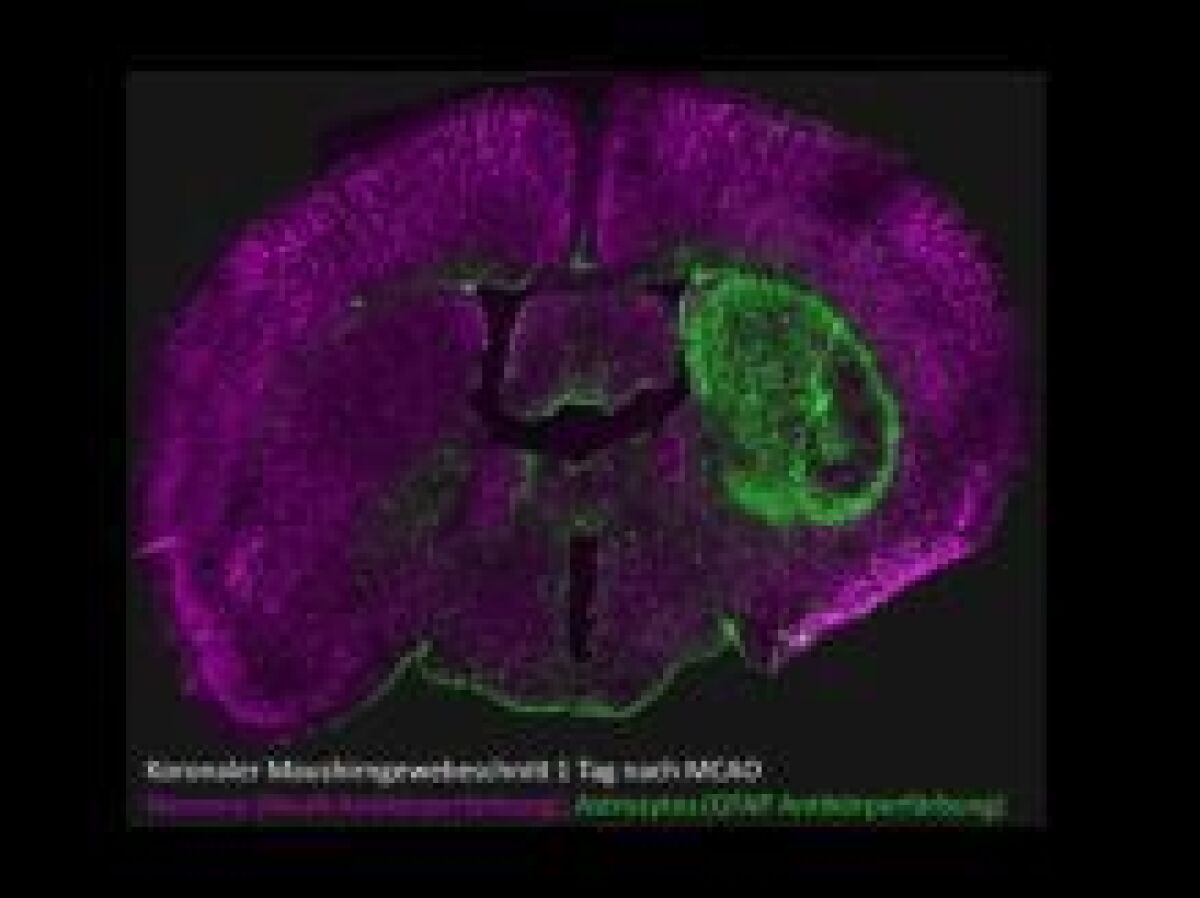

Schwerpunktthemen der Forschung an der Universitätsmedizin Essen sind Herz- und Kreislauferkrankungen, Immunologie und Infektiologie, Onkologie, Translationale Neuro- und Verhaltenswissenschaften sowie Transplantation. Der Großteil der am Zentralen Tierlaboratoriums Essen (ZTL) durchgeführten Tierversuche dient der Grundlagenforschung (40% der Tierversuche) zu diesen Schwerpunktthemen. Ein weitere Fokus liegt auf der translationalen Forschung (6% der Tierversuche). Das langfristige Ziel der Forschung an Tieren ist es, die Ursachen von Erkrankungen aufzudecken und neue Therapieansätze für Erkrankungen bei Mensch und Tier zu entwickeln.